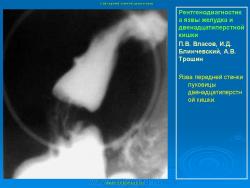

Пищеварительная система. Рентгенодиагностика язвы желудка и 12-ти перстной кишки. +

Рентгенодиагностика язвы желудка и 12-ти перстной кишки.

101.ya_.slayd45.jpg102.ya_.slayd46.jpg103.ya_.slayd16_1.jpg104.ya_.slayd17_1.jpg